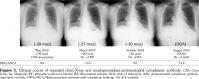

A 72-year-old female patient was admitted for rapidly progressive glomerulonephritis. Three years previously, she was first suggested to have interstitial pneumonia on health checkup. However, she did not visit the office because she was asymptomatic. One year later, the patient visited the hospital for exertional dyspnea. She also had noticed Raynaud’s phenomenon and sicca syndrome for several years. Chest X-ray showed permeability loss of the lower lung fields (Figure 1). High-resolution computed tomography of the lung showed ground-glass opacities with traction bronchiectasis in the peripheral lungs, without honeycombing, which was compatible with nonspecific interstitial pneumonia (Figure 2); at that time, laboratory test showed negative result of MPO-ANCA (<1.0 U/mL; normal <3.5 U/mL) (Figure 1). The test for anti-nuclear antibody was positive at 80 folds for homogeneous and speckled pattern (normal range <40 folds); however, the results for anti-topoisomerase, anti-centromere, anti-ribonucleoprotein, anti-ribonucleic acid polymerase III, and anti-Sjögren syndrome antigen A/Ro and anti-Sjögren syndrome antigen B/La antibodies were all negative. Accordingly, the diagnosis of interstitial pneumonia associated with rheumatic disorders was not considered likely. The results of bronchoalveolar fluid analysis, including cellular profiles, cytology, and culture for bacteria and mycobacterium, were not remarkable. Transbronchial biopsy showed no pathogenic findings. Therefore, patient was considered to have IIP. She was followed-up without therapy. Ten months before admission, she developed polyarthralgia and was suspected to have rheumatoid arthritis following a positive result for rheumatoid factor; at that time, testing for MPO-ANCA showed positive conversion, at 9.0 U/mL. The dipstick test, however, showed negative result for uric blood and protein. Therapy with tacrolimus and celecoxib alleviated her symptoms. Her medical history included cholecystectomy and lumbar compression fracture, and her medication regime comprised tacrolimus, celecoxib, famotidine, and sulfamethoxazole/trimethoprim. She denied a history of fever, sensory disturbance, or rash. On physical examination, body temperature was 36.3°C, blood pressure was 154/94 mmHg, and pulse rate was 95/minute. Respiration rate was 12/minute on room air. There were fine crackles on the lung bases and edema of the legs. No abnormal findings were observed on the heart, the abdomen, the skin or the neuromuscular system. Laboratory test results were as follows: white blood cell, 11130/μL (neutrophils 75.5%); C-reactive protein, 6.13 mg/dL; urea nitrogen, 42.2 mg/dL; creatinine, 4.23 mg/dL; urine protein, (2+); spot urine protein/creatinine ratio, 2.7; and 24-hour urinary protein excretion, 2.0 urine sediment showed urinary erythrocytes of >300/high-power field, red blood cell cast of 5-9/high-power field, and granular cast of 1-4/high-power field. The level of MPO-ANCA was highly elevated at 71.2 U/mL. X-ray of the hands did not show significant findings of erosion or joint space narrowing. A retrospective review of chest radiographs revealed slow progression of the pulmonary fibrosis (Figure 1). Computed tomography of the lung also revealed progression of pulmonary fibrosis. Renal biopsy showed necrotizing crescentic glomerulonephritis, leading to the diagnosis of microscopic polyangiitis (MPA). Methylprednisolone pulse therapy, followed by high-dose prednisolone, and intravenous cyclophosphamide improved renal function. Four months after therapy, the levels of urea nitrogen and creatinine were 29.8 mg/dL and 1.55 mg/dL, respectively. A spot urine protein/creatinine ratio was 2.4, while urinary sediment was inactive.